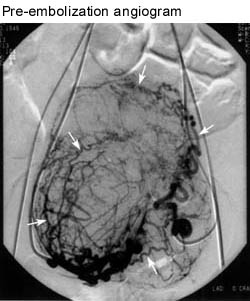

The blood shows up as black in these pictures. In this example both uterine arteries (there is one on each side) are being injected. The white arrows are pointing to the fibroids.